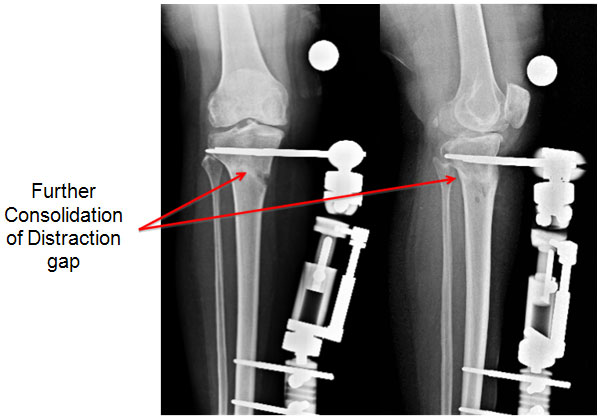

| 10 weeks |

| |